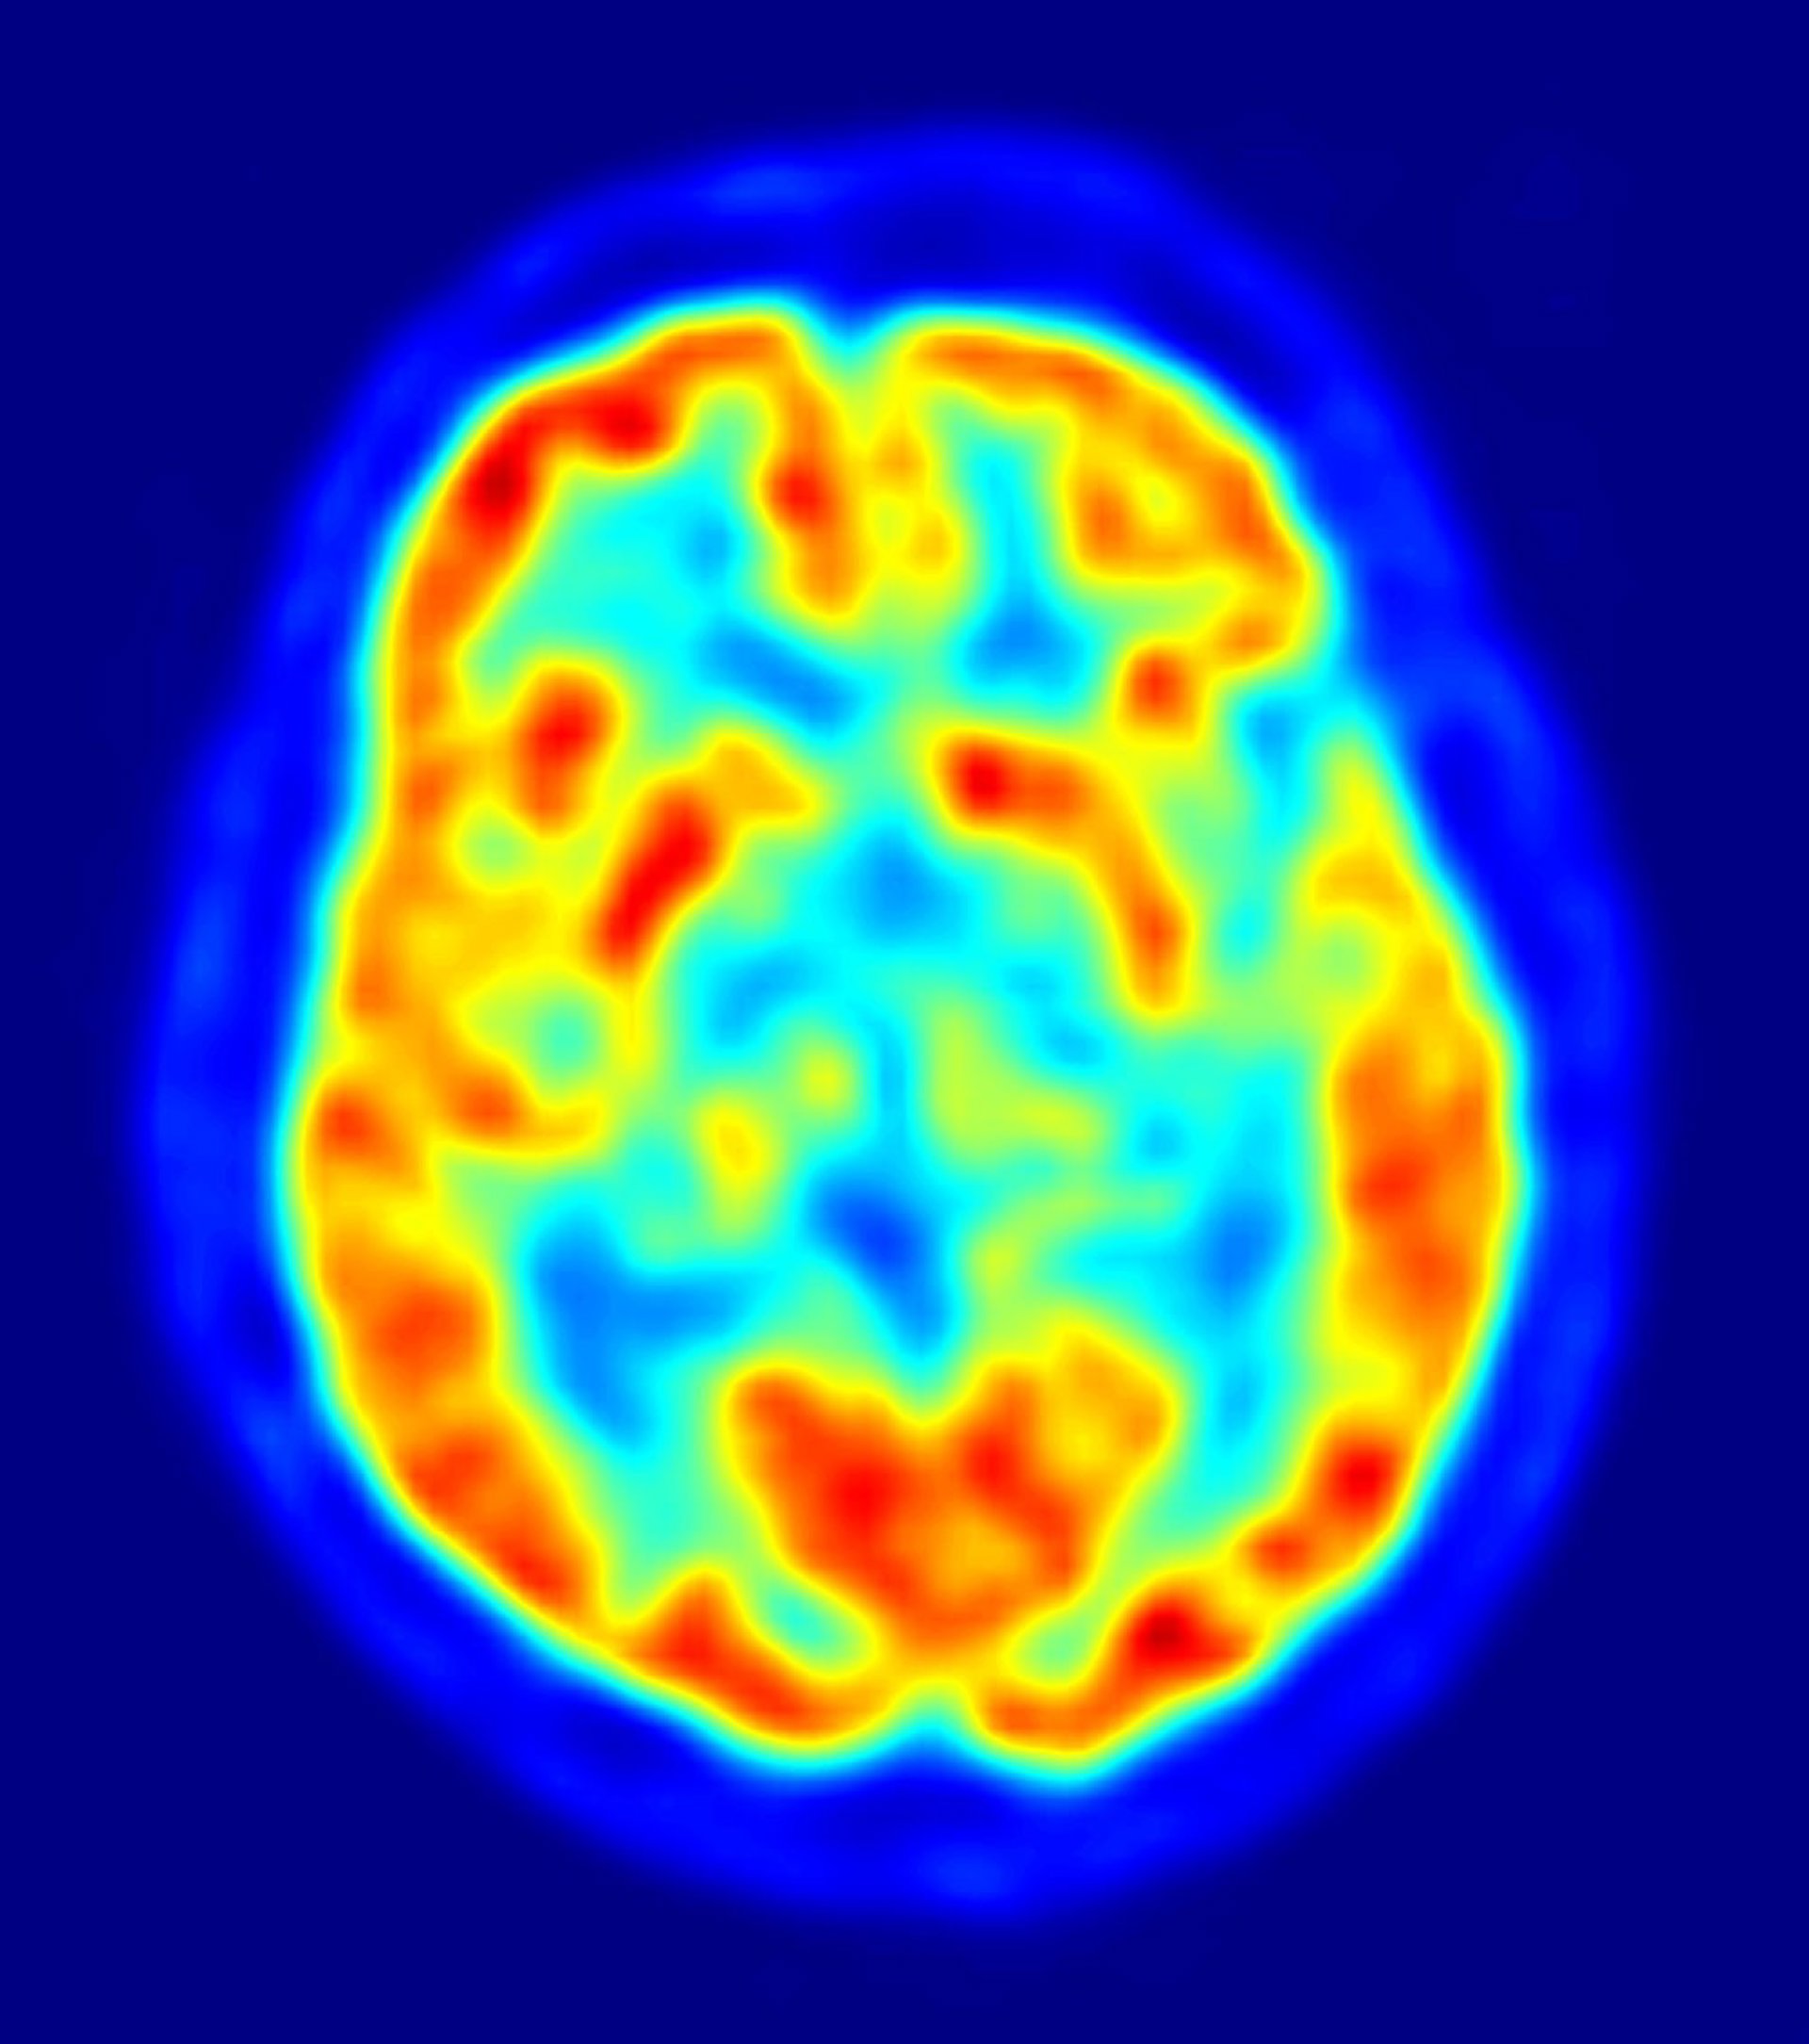

La mayoría de los genes asociados con enfermedades psiquiátricas se expresan antes del nacimiento en el cerebro humano en desarrollo, según un estudio publicado en 'Nature', encabezado por investigadores de la Universidad de Yale, en Estados Unidos. Además, los científicos han identificado cientos de diferencias genéticas entre hombres y mujeres, durante el proceso por el que sus cerebros toman forma dentro del útero.

La creación de cientos de miles de millones de células cerebrales, y el incalculable número de conexiones entre ellas, es una tarea tan compleja que el 86 por ciento de los 17.000 genes humanos estudiados participan en el proceso. El estudio evaluó no sólo qué genes están implicados en el desarrollo, sino dónde y cuándo se activan.

El estudio ha identificado los genes expresados ??en el cerebro humano -y cuándo y en qué parte del cerebro que se expresan- en 1.340 muestras de tejido de 57 sujetos de edades comprendidas entre los 40 días después de la concepción hasta los 82 años. El análisis proporciona un mapa sin precedentes de la actividad genética del cerebro en diferentes etapas de desarrollo.